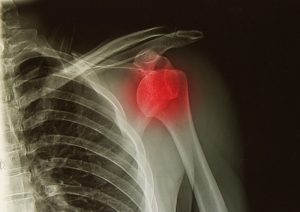

Shoulder pain is quite common in our society and interesting enough the symptoms of shoulder pain remind me of a light switch. Your symptoms are either “on” and you most likely experience pain in the shoulder with an inability to raise your arm in the air properly, or “off” with no shoulder pain and complete function […]